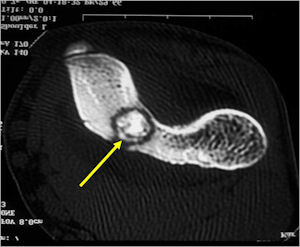

CT Scan:

- Well defined nidus with a smooth peripheral margin; +/- mineralization (CT more sensitive than XR and MRI for detecting mineralization); CT is better for detecting nidus in presence of exuberant sclerosis

- Osteoid Osteomas are Intermediate intensity on T1

- High intensity on T2 in areas of nidus and surrounding edema

- Reactive marrow edema may obscure the lesion on T2

- MRI is good for detecting synovitis and joint effusion with intraarticular osteoid osteomas